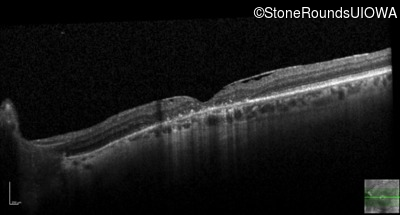

This 52 year old man had normal vision until his mid 30's when he began to have trouble distinguishing colors. the issuing 10 years he had a gradual loss of visual acuity accompanied by increasing photophobia.

| Age at visit: 55 years |

| Age at visit: 58 years |

| Age at visit: 61 years |

| Age at visit: 64 years |